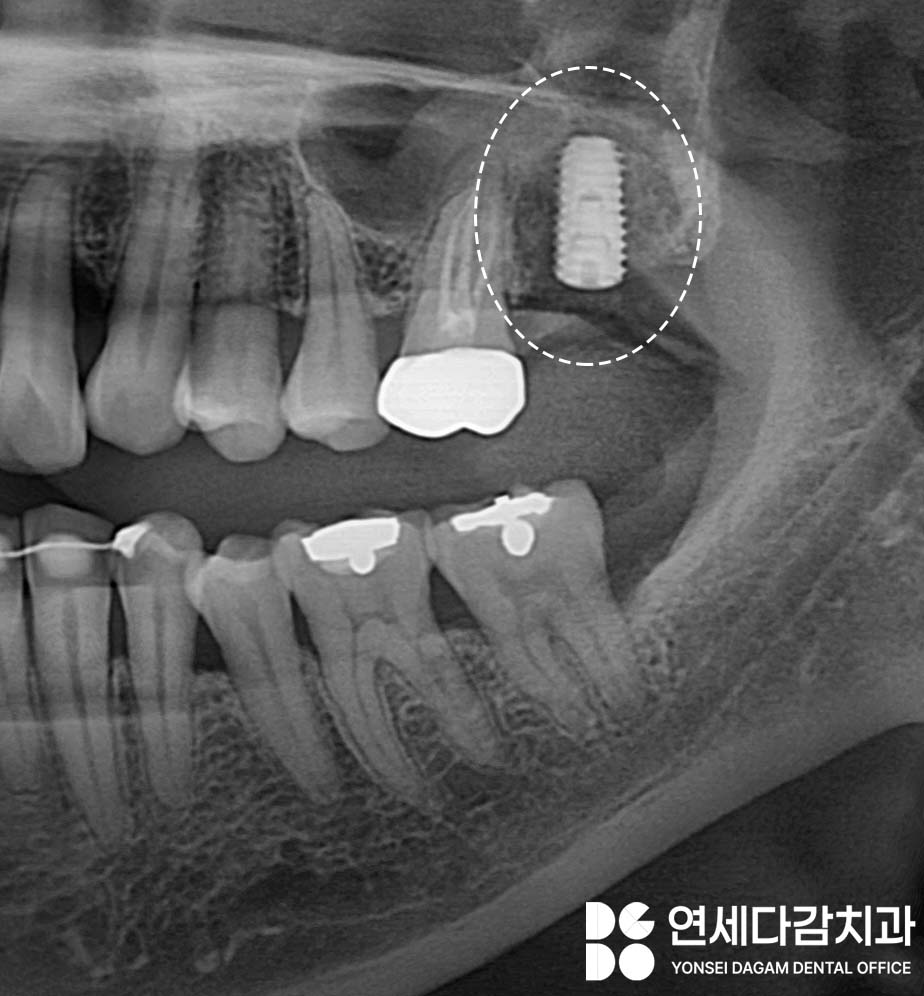

따라서 발치 후 임플란트 같은

치료를 통해 회복이 필요한 상황인데,

수면 진정 치료를 통한

임플란트 식립이 완료된 후에는